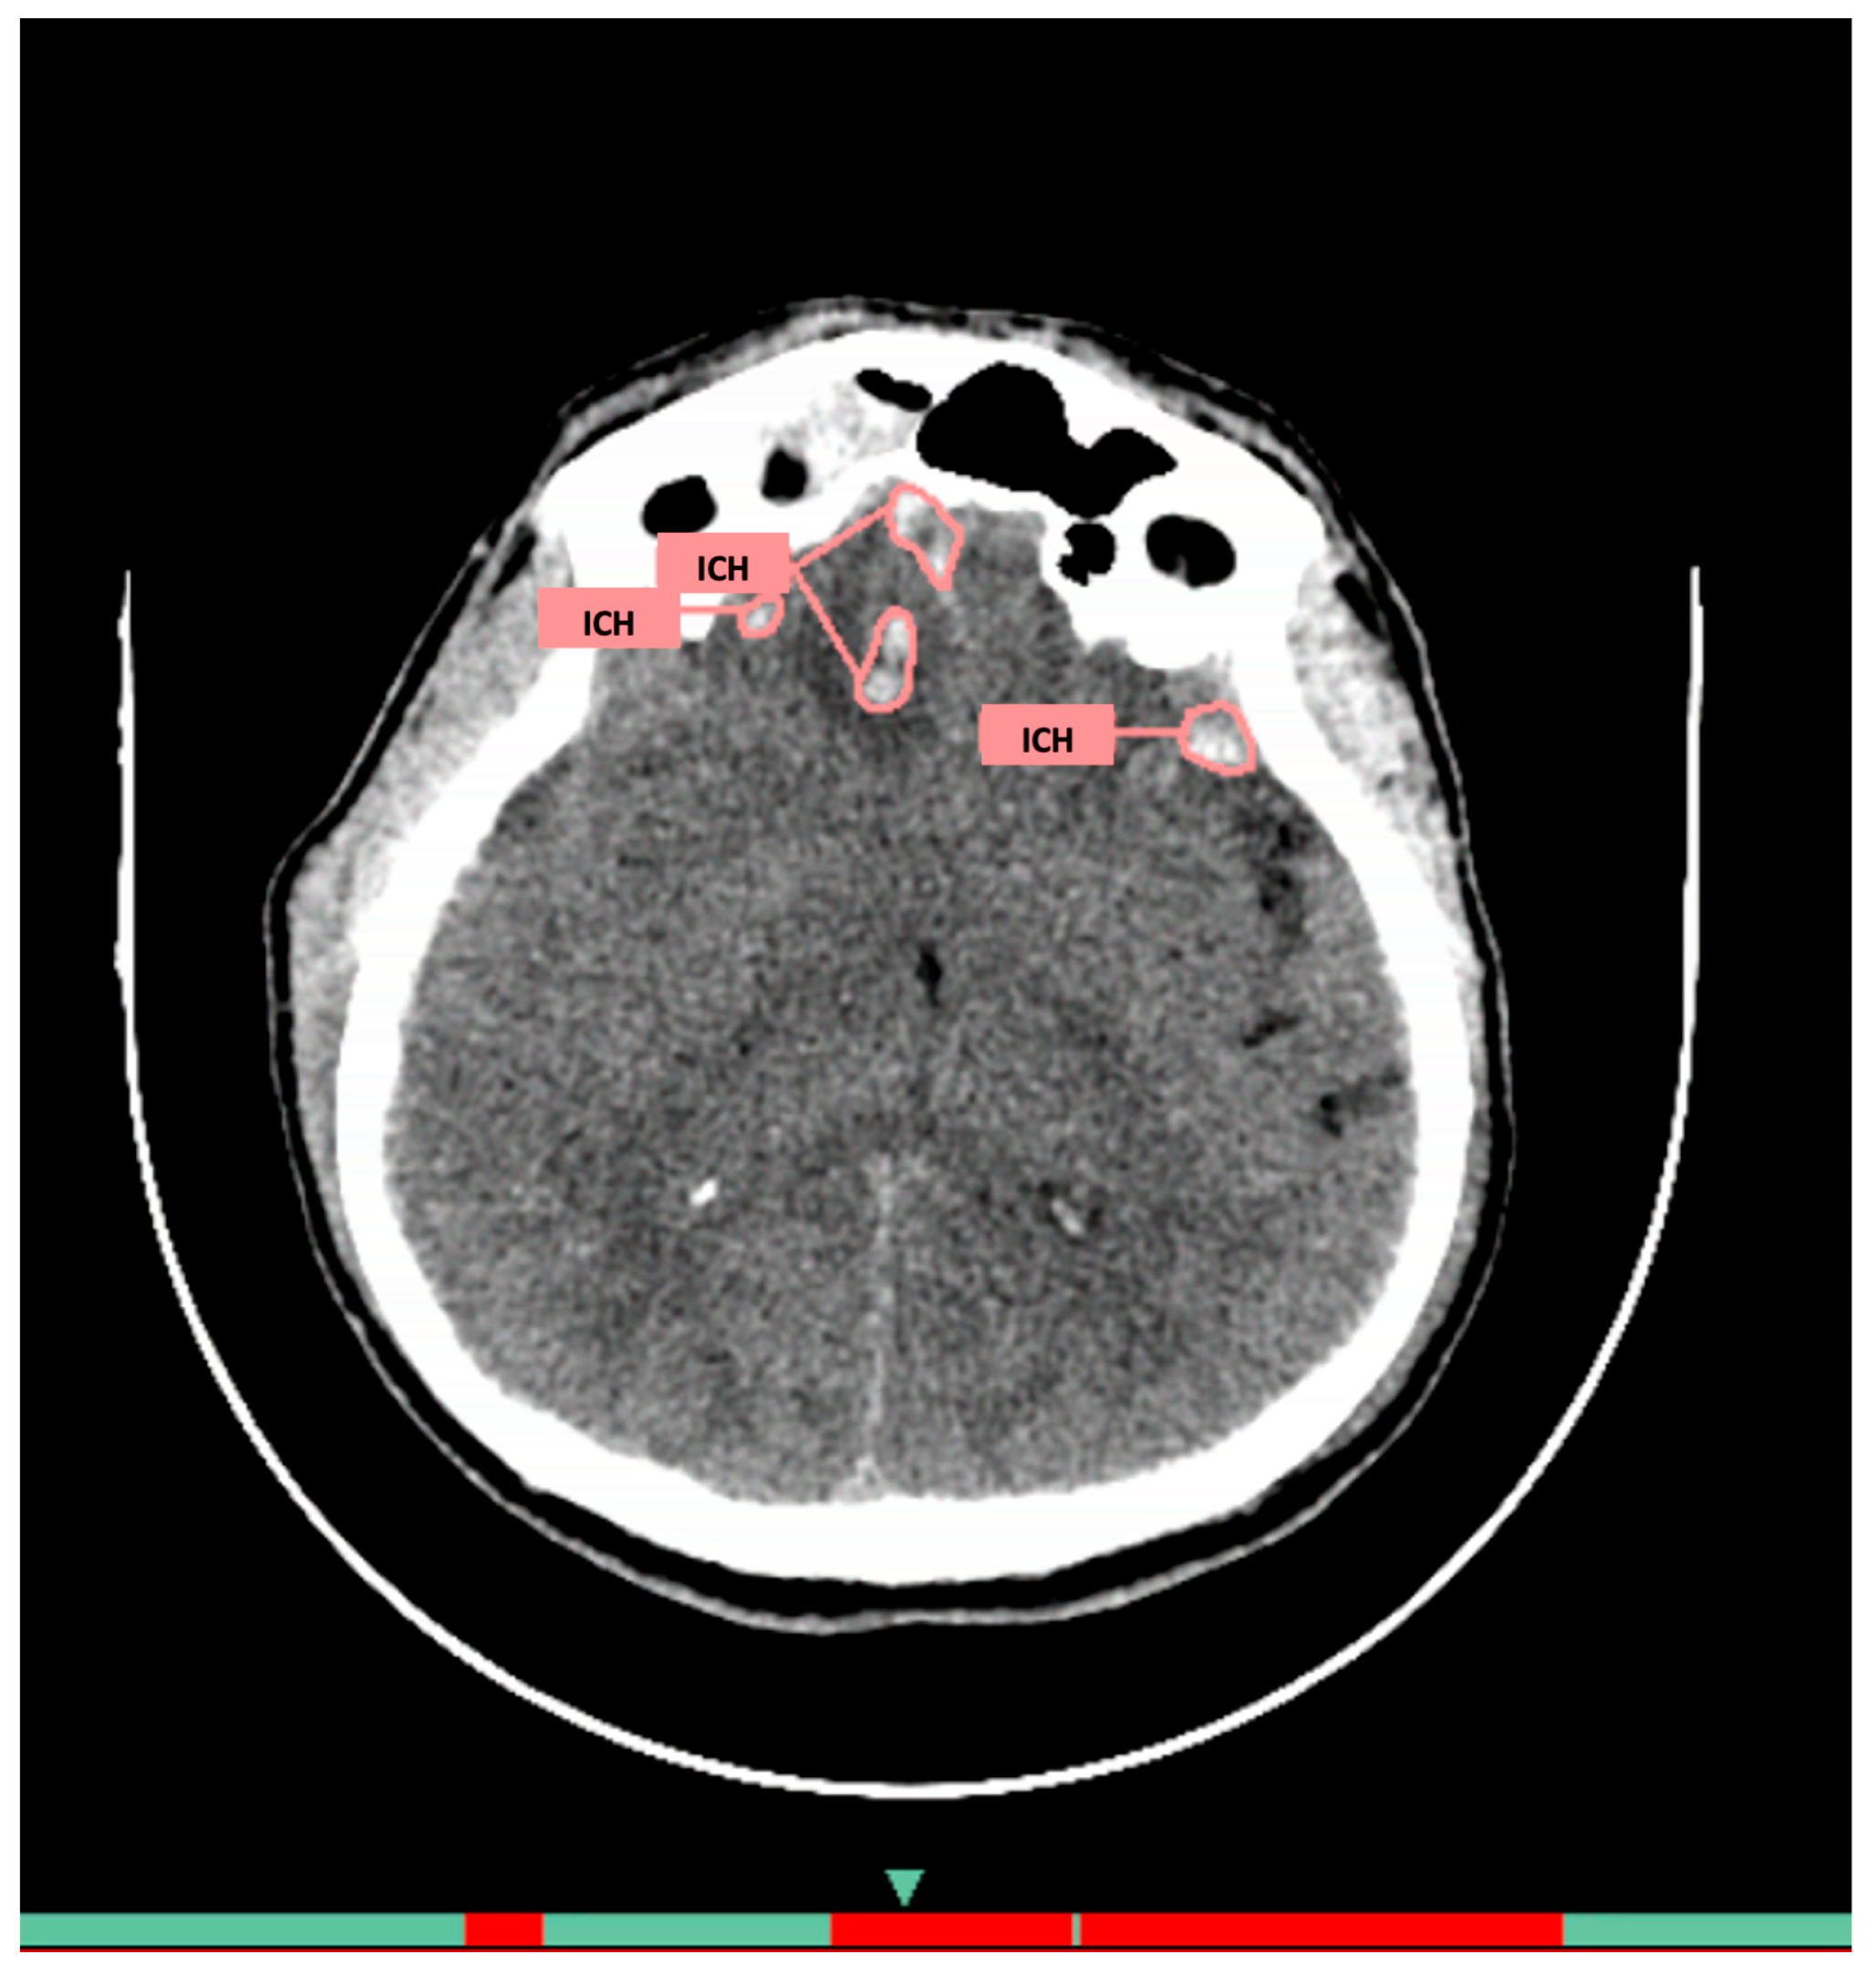

- Hyperdense foci in brain parenchyma, meningeal spaces, or ventricular system (epidural, subdural, subarachnoid, and intracerebral localization);

- Density > 40 HU for acute hemorrhages;

- Exclusion of calcified areas;

- Minimum registered hemorrhage volume: 1 mm3.